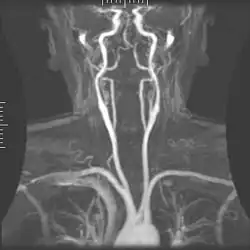

Angiography

Magnetic resonance angiography (MRA) generates pictures of the arteries to evaluate them for stenosis (abnormal narrowing) or aneurysms (vessel wall dilatations, at risk of rupture). MRA is often used to evaluate the arteries of the neck and brain, the thoracic and abdominal aorta, the renal arteries, and the legs (called a "run-off"). A variety of techniques can be used to generate the pictures, such as administration of a paramagnetic contrast agent (gadolinium) or using a technique known as "flow-related enhancement" (e.g., 2D and 3D time-of-flight sequences), where most of the signal on an image is due to blood that recently moved into that plane (see also FLASH MRI).[53]

Techniques involving phase accumulation (known as phase contrast angiography) can also be used to generate flow velocity maps easily and accurately. Magnetic resonance venography (MRV) is a similar procedure that is used to image veins. In this method, the tissue is now excited inferiorly, while the signal is gathered in the plane immediately superior to the excitation plane—thus imaging the venous blood that recently moved from the excited plane.[54]